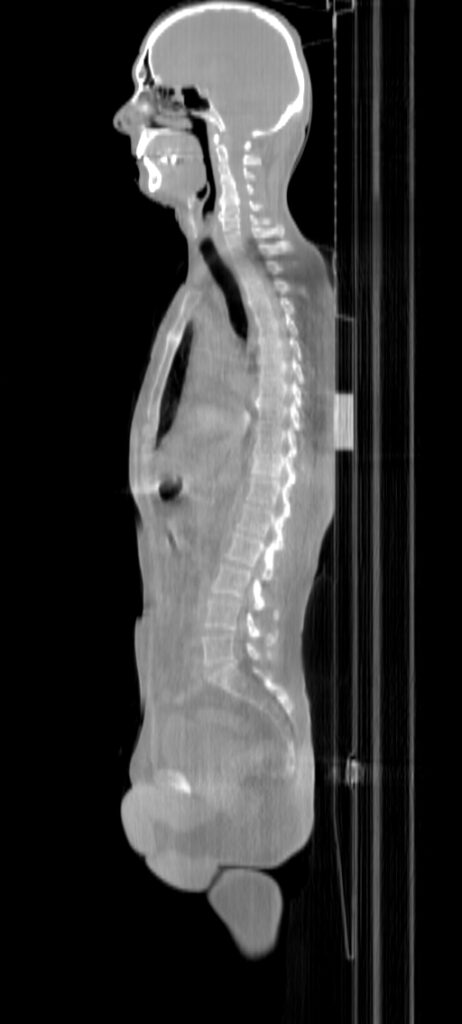

Planning CT Images

PTV(s) Volume, Length

27500 cc, 84 cm

Scan Length

84 cm / 1 min